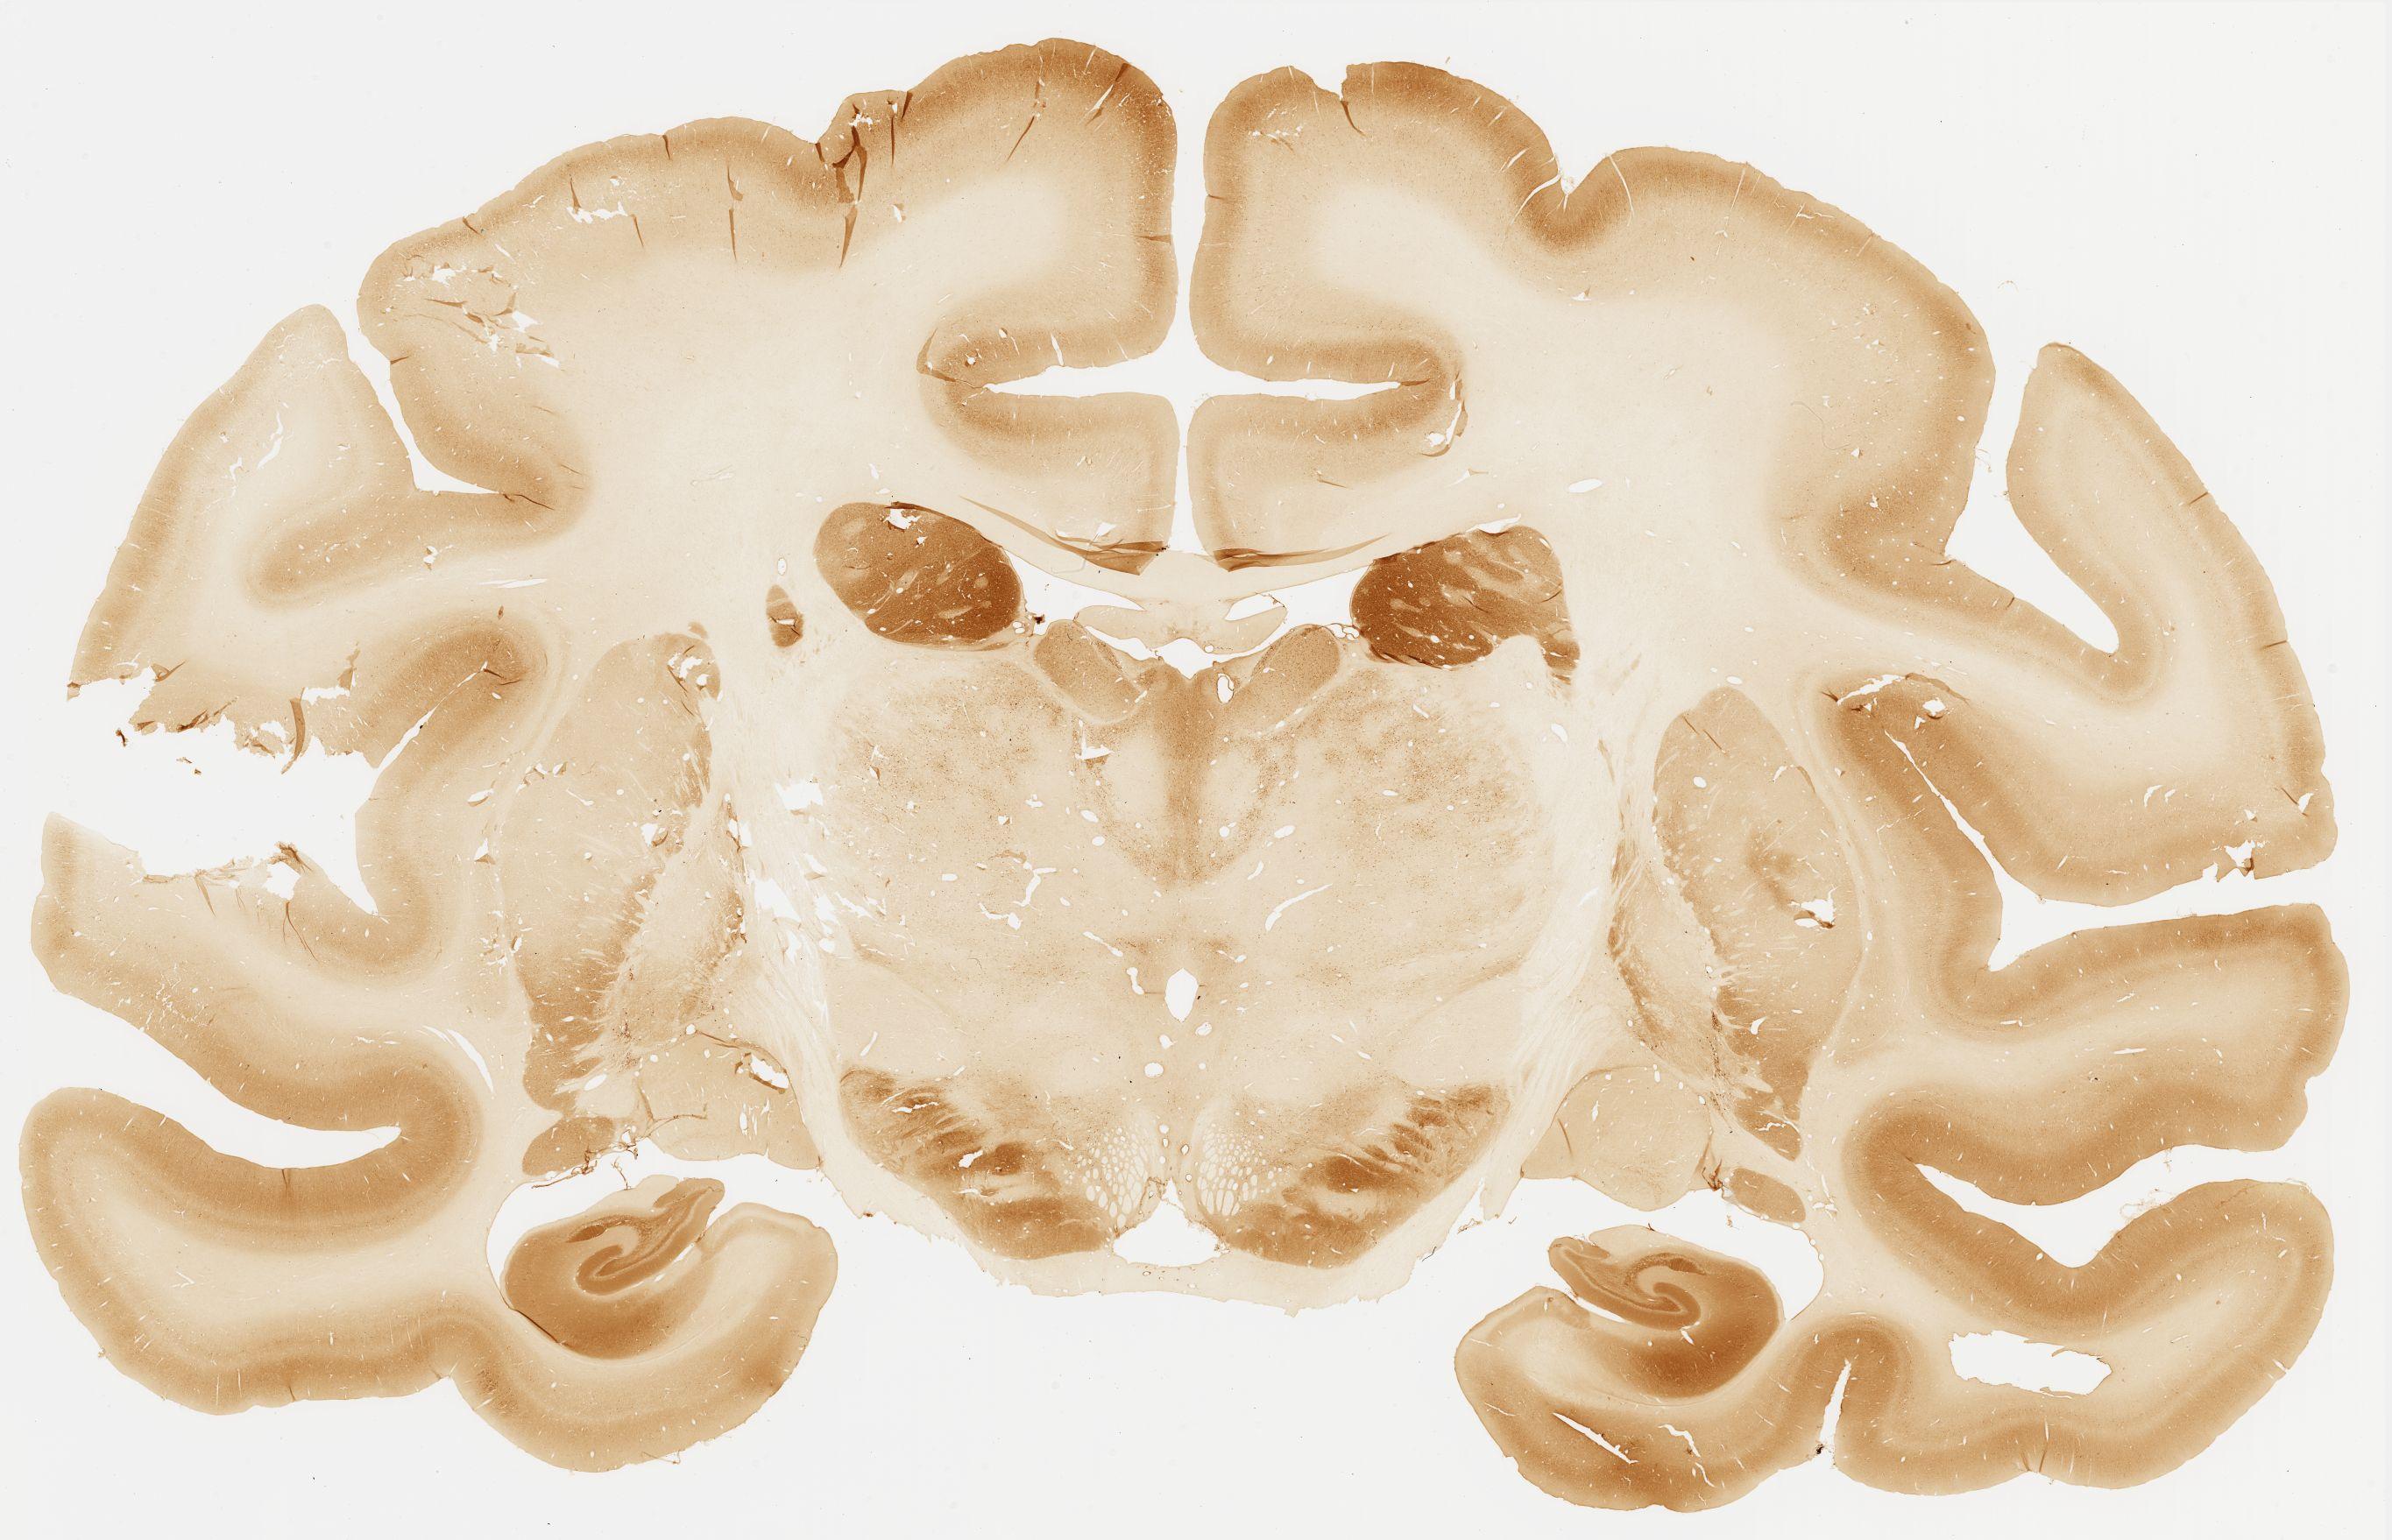

Datasets -> Macaca Fascicularis -> Calb, (Calbindin), coronal, immuno, Whole-Brain, adult

[ Metadata ]   ·   Source: Edward G. Jones

thumbnail

106